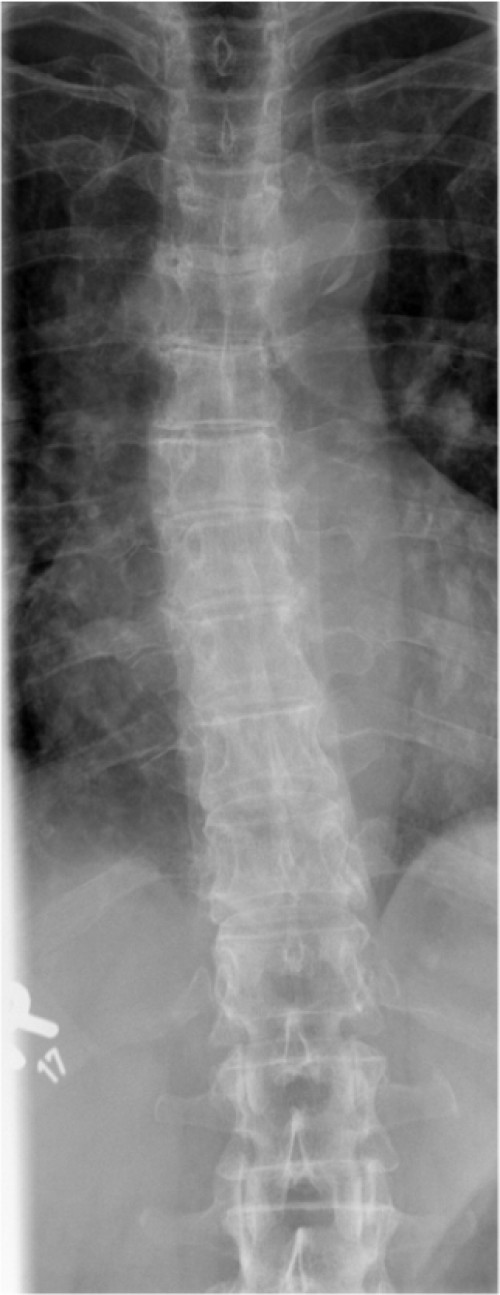

ICD: S22.04

Eine 66-jährige Patientin stellt sich in der Notfallambulanz vor und berichtet von einer Leiter gestürzt zu sein. Sie habe für ihren Enkel Lego-Spielzeug vom Dachboden holen wollen und sei dabei von der Leiter gerutscht. Sie sei auf ihren beiden Fersen gelandet und anschließend auf den Rücken gefallen. Der linke Fuß sei seitdem nicht belastbar, der rechte Fuß schon. Am rechten Fuß sei jedoch eine Schwellung im Bereich der Sprunggelenke sichtbar geworden.